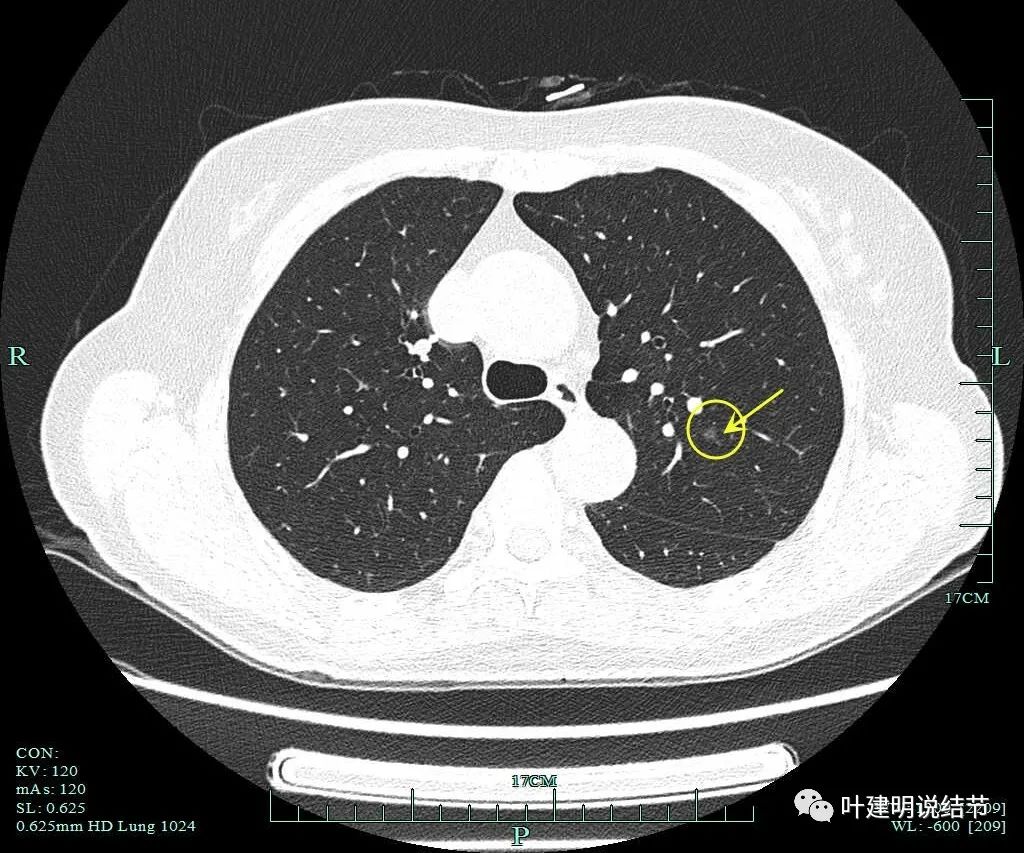

病灶10:左上叶微小磨玻璃结节,似见微小血管进入,边缘略模糊,考虑肺泡上皮增生或不典型增生可能性大,位置不好,靠肺门较近,难以楔形切除,可先随访。

病灶2重建后显示瘤肺边界清以及血管进入。